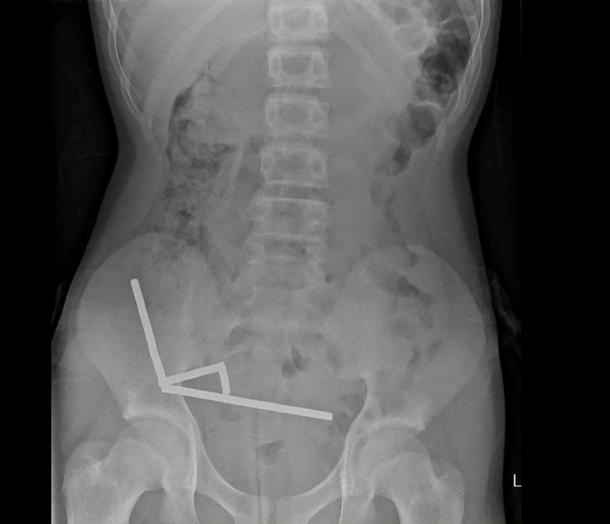

This undated handout released on October 24, 2025 from the New Zealand Medical Journal (NZMJ) shows an x-ray image of pieces of high-power magnets clumped up in the intestines of a New Zealand teenager in Tauranga

An X-ray showed the magnets had clumped together in four straight lines inside the child’s intestines.

“These appeared to be in separate parts of bowel adhered together due to magnetic forces,” they said.